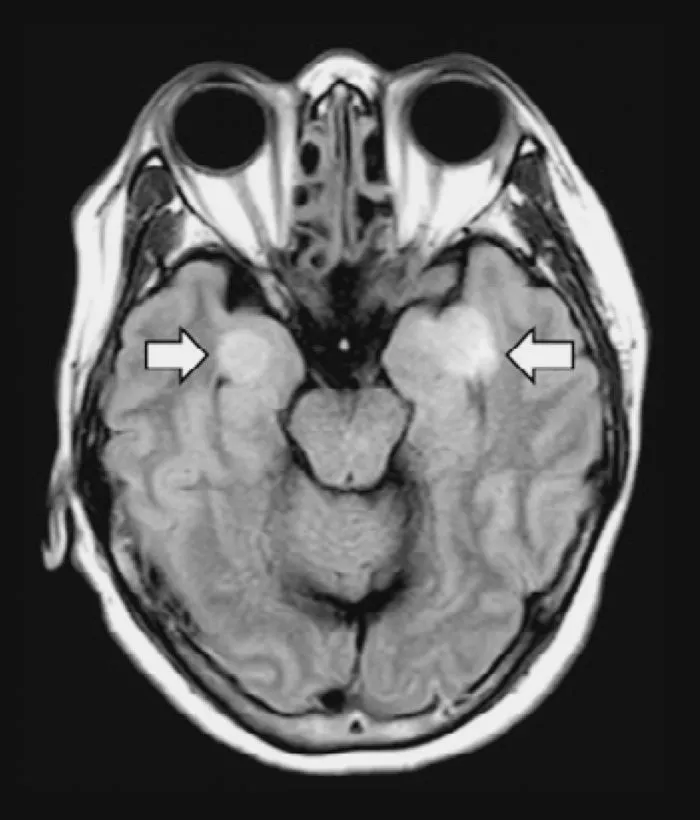

从大脑到脚趾,新冠是如何一步步对器官“下手”的?

一名患有COVID-19的58岁女性患了脑炎,导致大脑组织受损(箭头)。图片来源:《科学》杂志